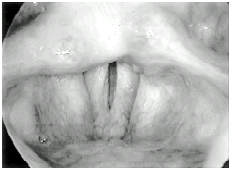

O exame de quimografia deve ser realizado da mesma maneira que a laringoscopia com o telescópio. O paciente deve estar na posição sentada, com o mento ligeiramente elevado e a língua exposta confortavelmente. O examinador deve fixar a língua com o dedo polegar e o médio, tracioná-la delicadamente e introduzir o telescópio. A emissão das vogais /e/ ou /i/, durante a fase de introdução do telescópio, amplia o espaço na região da orofaringe, facilitando sua introdução e, conseqüentemente, a visualização da laringe. Uma vez visualizada a laringe em imagem convencional, a região da glote a ser examinada com a quimografia deve ser escolhida (Figura 1a). Em seguida, o telescópio deve ser mobilizado de tal forma que o limite superior da imagem visualizada no monitor venha a ser a região da glote selecionada para o exame (Figura 1b). Nesse momento, o pedal deve ser acionado, obtendo-se, com isso, a imagem quimográfica (Figura 1c). Essa imagem mostra, claramente, os ciclos vibratórios que se sucedem em tempo real, captando todos os ciclos vibratórios. Podemos visualizar os ciclos vibratórios e as 4 fases que compõem cada um destes ciclos: a fase fechada, a fase de abertura, a fase de abertura máxima e a fase de fechamento. Em cada um desse ciclos, podemos ainda observar os diversos parâmetros que os caracterizam como: a amplitude de vibração de cada prega vocal, simetria de fases, estado da onda de mucosa em cada lado (lábio superior e inferior), fechamento glótico e tempo de duração de cada fase do ciclo vibratório. Ainda: ao observarmos a sucessão dos ciclos vibratórios, podemos perceber a periodicidade regular ou não da vibração. A Figura 3 mostra, esquematicamente, esses diversos parâmetros da vibração cordal visualizados pela quimografia.

Figura 1 a. Imagem completa das pregas vocais obtida no modo convencional.

Figura 1 b. A linha escaneada corresponde à primeira linha superior da imagem.

Figura 1 c. As linhas escaneadas são apresentadas sucessivamente no monitor - vibração normal.